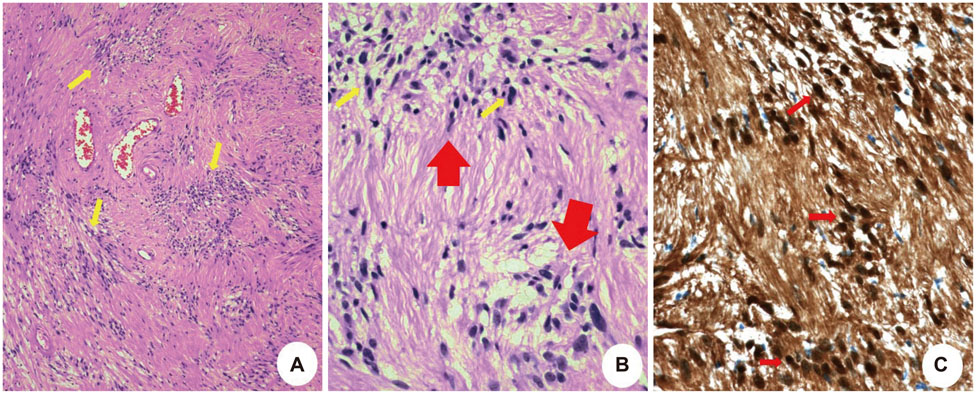

- The olfactory groove schwannoma is a quite rare tumor. We report a case of a 49-year-old woman with an olfactory groove schwannoma attached to the cribriform plate without olfactory dysfunction. She had no specific neurological symptoms other than a headache, and resection of the tumor showed it to be a schwannoma. About 19 months after the operation, a follow-up MRI showed no evidence of tumor recurrence. Surgical resection through subfrontal approach could be one of the curative modality in managing an olfactory groove schwannoma. An olfactory groove schwannoma should be considered in the differential diagnosis of anterior skull base tumors.